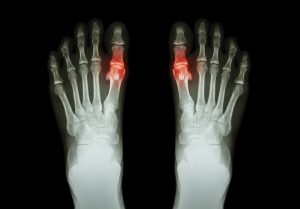

Gigt er en tilstand, der er frembragt ved akkumulering af mikroskopiske krystaller af urinsyre i leddene. Disse krystaller udgør buler under huden eller deponeres i urinvejen.

Men når denne eliminering ikke virker, stiger urinsyre niveauerne unormalt. Krystaller dannes og deponeres i leddene, hvilket giver mulighed for episoder med skarp smerte.

- Indledningsvis kan kun ét eller flere led blive påvirket. Dette har tendens til at være stortåen, knæet eller ankelen. Dette angreb kan forsvinde i løbet af et par dage, men kan vende tilbage endnu en gang i et stykke tid.

- Det berørte led er typisk varmt og rødt (betændt). Generelt har det også tendens til at være følsomt og hævet.

Nogle mennesker udvikler kronisk gigt. Dette kan føre til ledskader og tab af mobilitet i visse led.